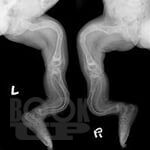

В учебном пособии подробно освещены вопросы эмбриогенеза трубчатых костей, нарушения их развития и формирования, дана подробная классификация нарушений дизонтогенеза. Описаны основные нозологические формы дизонтогенетических нарушений, наблюдаемых в клинической практике. Освещены вопросы кровоснабжения длинных трубчатых костей и репаративной регенерации при их переломах.